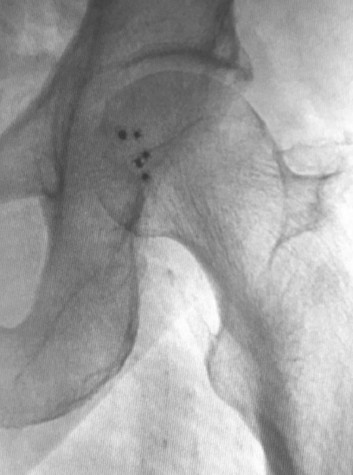

Celt ACD® allows multiple immediate re-sticks in calcified arteries.

5 Celt ACDs